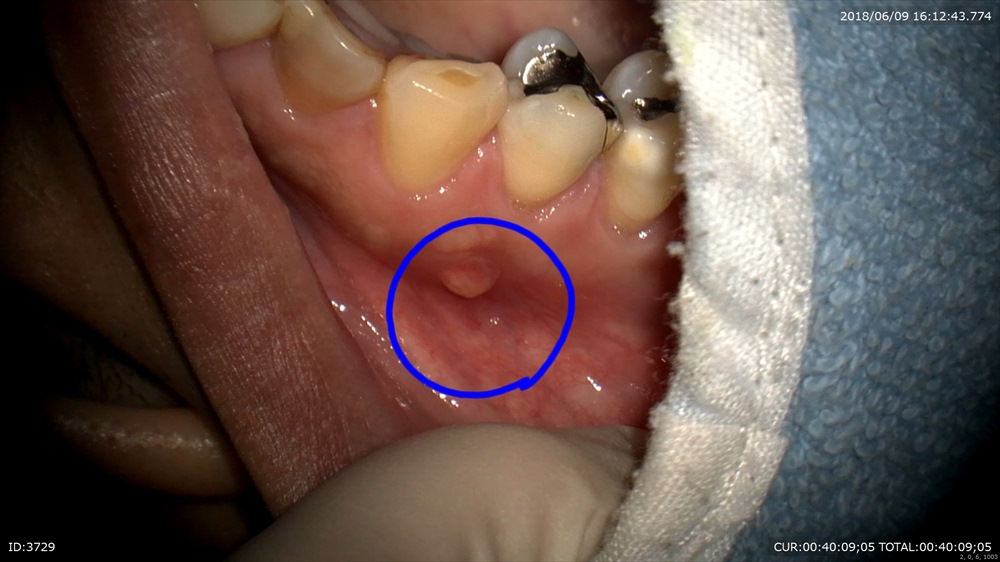

こんなに腫れて違和感がすごい。との事。顔を洗う時にも気になる位でした。

基本に忠実に

無痛で。細菌除去。